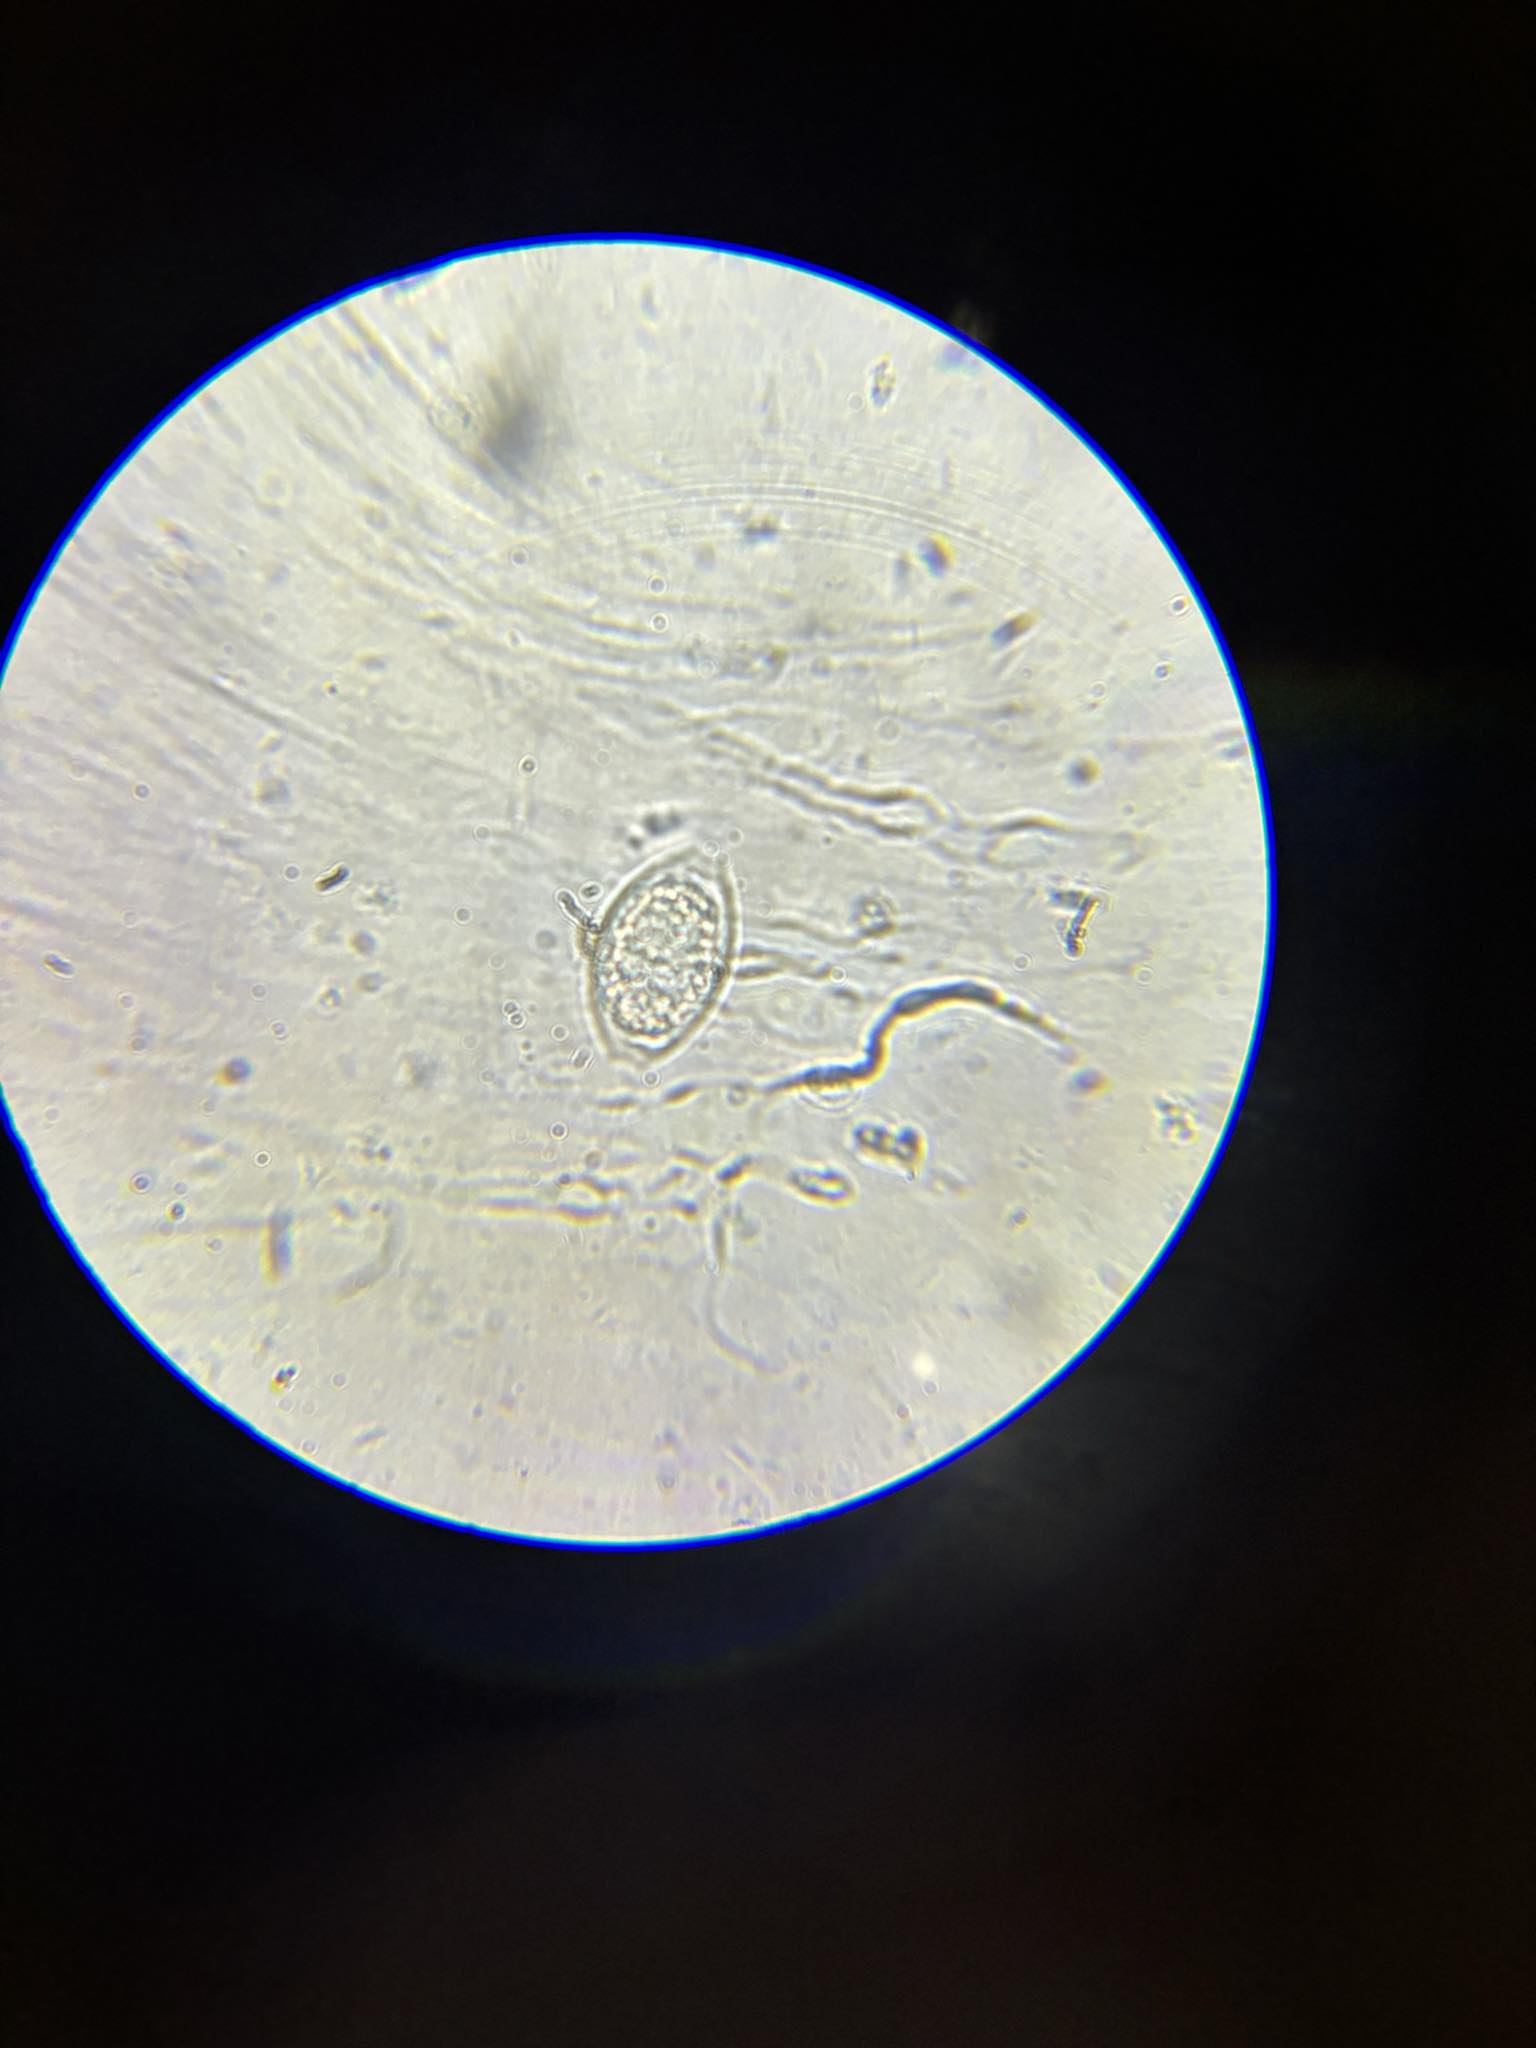

giardia intestinalis cysty